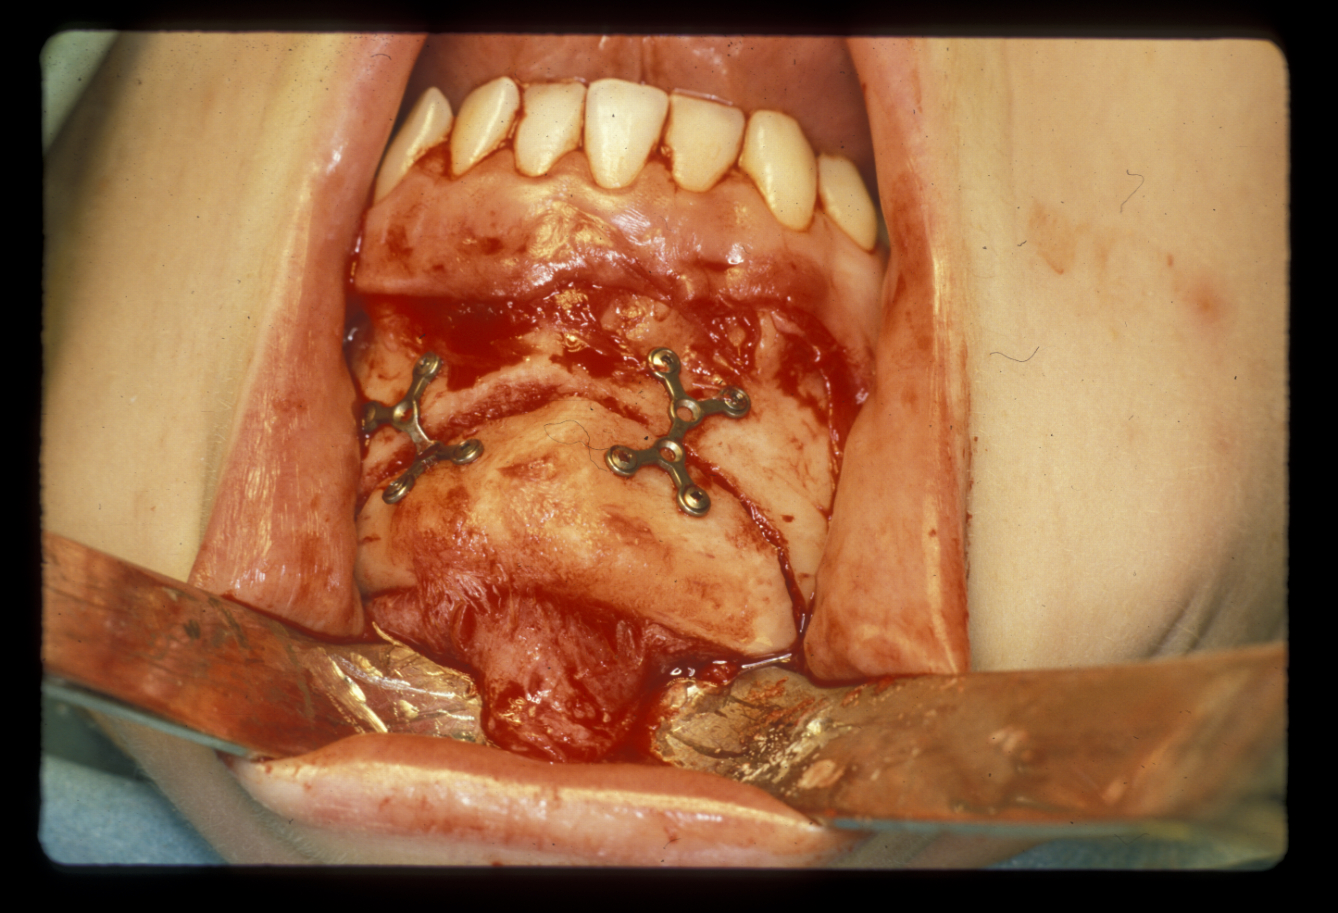

The chin is approached from an intraoral incision that exposes and protects the mental nerves. Bone cuts are made horizontally to retain the lingual muscle attachments. The chin is reduced by excising a middle portion of bone and inset to preserve the aesthetics of the cortical chin shape. It can be advanced by sliding forward. It is internally fixed using miniplates (Figure 11). Small asymmetries can be corrected in this way.

Augmentation genioplasty uses implants, either made from synthetic materials or a bone graft taken from the hip. The implant can be inserted by a skin incision under the chin (which is invisible from a front view) which is preferable for inert non-biological implants which have a lower inherent resistance to infection. Iliac crest grafts or sliding advancement genioplasties are far more common and a number of specific intra-oral miniplates have been devised to aid this surgery which also has a role in managing obstructive sleep apneoa. Almost inevitably, the aesthetic results using somebody’s own bone are superior to those achieved by using synthetic materials.